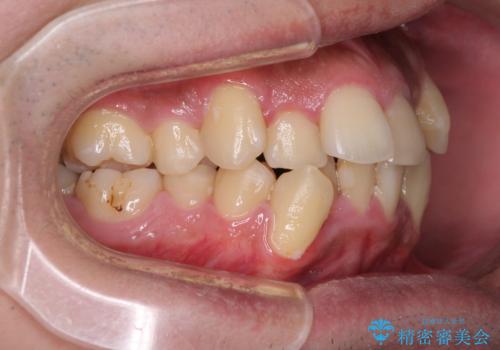

上下左右の犬歯が八重歯になっており、口元にもやや突出感があるため、上下左右の小臼歯4本を抜歯し、ワイヤー装置にて矯正治療を行うこととしました。

右上第一小臼歯は歯根癒着により移動せず、左上第二小臼歯は移動はするものの非常に動きが鈍かったため、抜歯したスペースを閉じるまでに非常に時間がかかってしまいました。